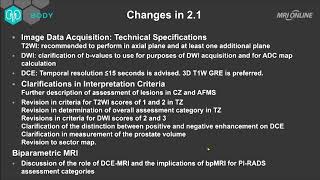

Prostate MRI Introduction Multi-parametric Prostate MRI using PI-RADS v 2.1: an Introduction

Multi-parametric Prostate MRI using PI-RADS v 2.1: an Introduction Prostate MRI: Introduction PI-RADS v2.1 on MRI

Prostate MRI: From Principles to Performance PI-RADS v2 and v2.1: Interobserver Agreement and Diagnostic Performance in PZ and TZ lesions

PI-RADS v2 and v2.1: Interobserver Agreement and Diagnostic Performance in PZ and TZ lesions